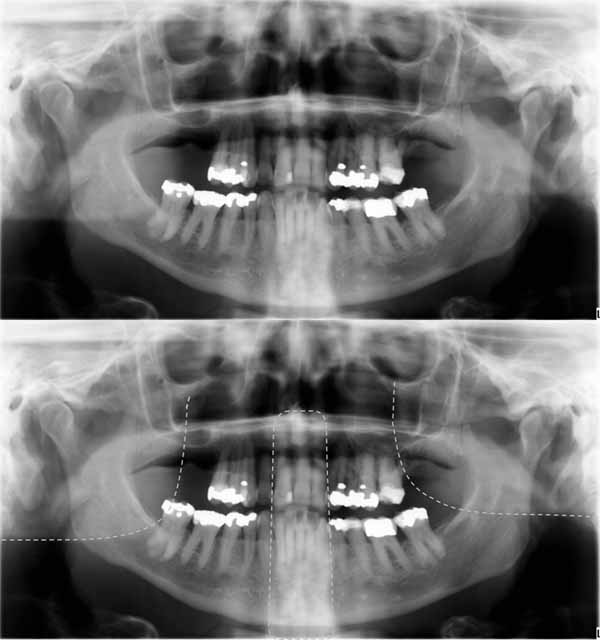

ゴースト

ゴーストはパノラマ画像を撮影するときに発生する歪みの1つであり、画像を確認するときに考慮する必要があります。簡単に説明すると、ゴースト画像とは、画像が撮影されたときに、画像化された顎の反対側にあった構造の画像です。これらの構造は、画像の反対側にぼやけて拡大されて表示されます。

ゴーストの最も明確な例の1つは、下顎底です。たとえば、下顎の右側を撮影する場合、X線放射は下顎の左側も通過する必要があります。この場合、下顎の左側は焦点レイヤーの外側にあるため、この構造の不明瞭なゴースト画像が右側の画像に重なって表示されます。もう1つの例は頸椎です。頸椎の場合、前歯が描かれると顔の前部と顎の上にゴースト画像が作成されます(画像30を参照)。これらのゴースト画像により、パノラマX線画像での診断が困難になります。